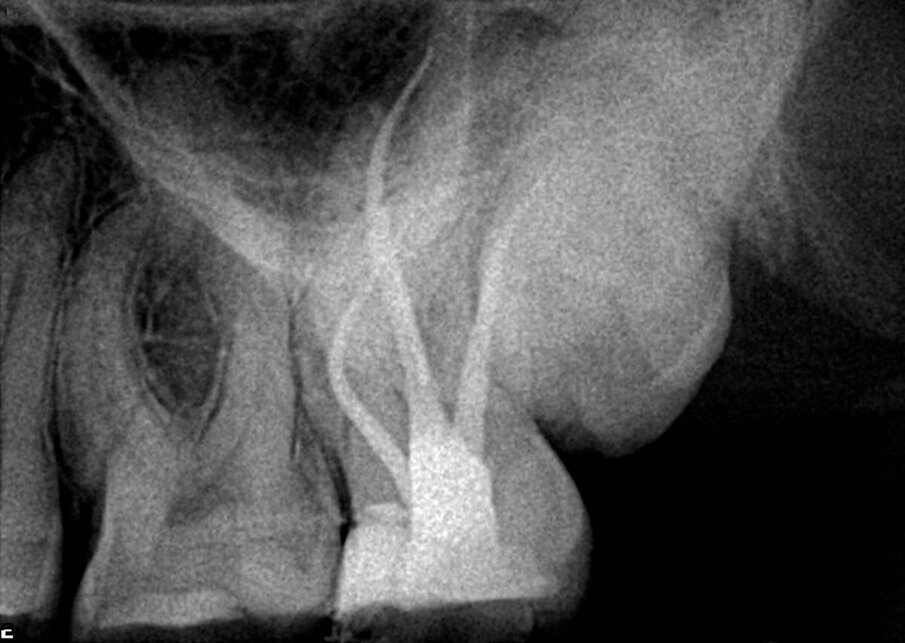

U ovom primeru, pacijenta je uputio njegov stomatolog, koji je ušao duboko u koren u pokušaju da pronađe kanale i nije bio uspešan, ali na sreću nije došlo do perforacije (Sl. 8). Pod mikroskopom i uz pomoć ultrazvučnih nastavaka, kanali su bili dostupni. Na rendgenskom snimku vidimo da su kanali, posebno mezijalni, uski i imaju male krivine, posebno apikalno. Pravi izazov u ​​ovom slučaju bio je održavanje prvobitnog oblika kanala. Iz tih razloga je izabrana sekvenca sa konusom od 0.04. Tretman je započet sa Traverse otvaračem 25/0.08, nakon čega je usledio 8 K-File za određivanje radne dužine. Korišćene su Traverse turpije 13/0.06 sve do kraja radne dužine, a zatim su usledile ZenFlex turpije 20/0.04 i 25/0.04, obe dovedene do radne dužine. Za apikalno proširenje korišćena je ZenFlex turpija 30/0.04.

Kao glavni konus u distalnom korenu korišćen je srednji konus, a u mezijalnom korenu su korišćeni fini srednji konusi. Tokom tretmana korišćena je puna sekvenca irigacije, a sistem, koji je uključivao duboki istmus između mezijalnih korena, ispunjen je u više nivoa od sredine do vrha, čime je postignuta prelepa 3D obturacija (Sl. 9).